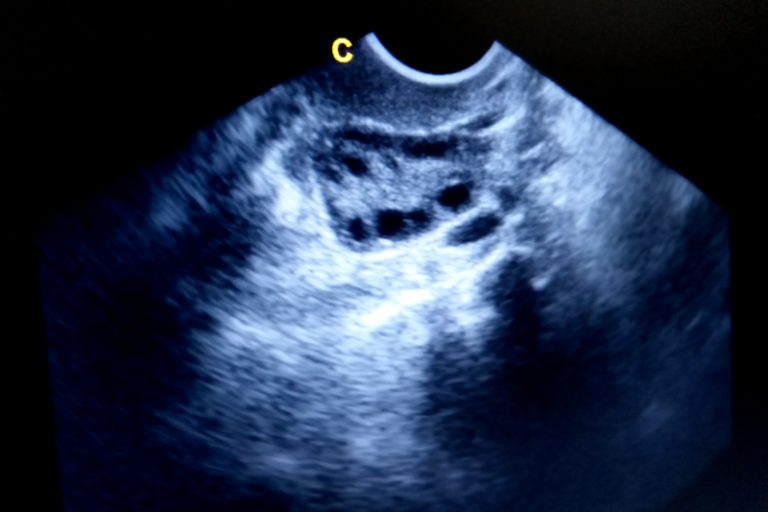

李太今年三十五歲,五年前服食排卵丸成功懷孕,生了一個小寶寶之後,一直沒有避孕想多要一個孩子,可是遲遲懷不上。「醫生,我有多囊卵巢症,上胎都要靠食藥才受孕,平時經期都不來,要吃催經藥。」我看她體形適中,不似多數患者體重超標,但體重指標( BMI)在正常水平的人也會受「多囊卵巢症」困擾。我替她檢查,超聲波顯示卵巢增大,每邊卵巢有三十多個細小的卵泡。加上她經期不準,臨床診斷為「多囊卵巢症」。